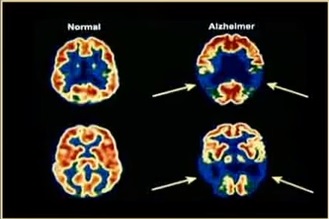

Plusieurs études mettent en avant l’effet positif des cannabinoïdes sur les neurones affectés des souris génétiquement modifiées et avec Alzheimer. Cette maladie neurodégénérative se développe suite à l’accumulation de la protéine bêta-amyloïde en « plaques » sur le cerveau, et a pour conséquence d’endommager les neurones au point d’atteindre la mémoire. Les études n’ont pas seulement été réalisées sur les souris modifiées génétiquement, mais aussi sur celles à qui l’ont a injecté la protéine pour stimuler la formation de la plaque de protéine. Dans le premier groupe, le CBD était la clé, alors que dans le second, le THC semblait être une bonne solution pour contrôler cette maladie.

Comme nous le savons déjà, le CBD est un cannabinoïde non psychactif, c’est d’ailleurs ce qui lui permet d’être classé comme « cannabinoïde médicinal ». Il possède bien plus de propriétés, dont celle d’être un puissant antiinflammatoire, vertu très appréciée des patients qui ont des troubles liés à une inflammation. Le THC, lui, prévient les dommages sur la mémoire causés par la protéine bêta-amyloïde, mais pas seulement, puisqu’il prévient également la formation des plaques. Jusqu’en 2006 il était reconnu à niveau mondial comme le meilleur médicament pour les patients d’Alzheimer selon les résultats.